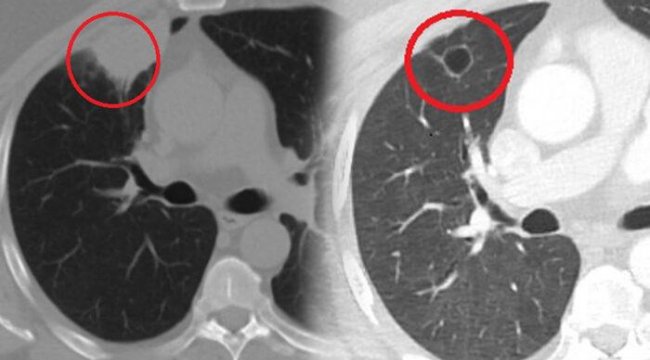

"Hastamız, çalıştığı başka bir kentte göğsünden darbe alıyor ve ağrıları geçmeyince bir üniversite hastanesine başvuruyor. Burada hastaya bir akciğer grafisi çekiliyor. Sağ akciğerinde bir kitleye rastlanıyor. Daha sonra hastaya, bir akciğer tomografisi çekiliyor ve göğüs cerrahisi için önemli büyüklükte olan 4 santimetre çapında, akciğer kanserine benzer özellikte radyolojik bulgular olan bir kitle tespit ediliyor. Daha sonra hastaya yapılan ileri tetkiklerde akciğer kanseri teşhisi konuluyor. Hastaya bir cerrahi planlanıyor. Hasta Kahramanmaraşlı olduğu için kendi memleketine gelmeyi tercih ediyor. Bize başvurdu ve göğüs ağrısı şikayeti vardı. Öksürük, nefes darlığı, balgam çıkarma, ateş gibi şikayetleri yoktu. Hastayı biz de değerlendirdik ve ameliyat olmasına karar verdik. Çünkü akciğer kanserine çok benzer radyolojik bulguları vardı. Sağlık Bakanlığımızın kuralları gereği her hastayı ameliyat öncesi PCR testi yapılır. Biz de ameliyat gecesi hastadan PCR testi aldık ve testi pozitif geldi. Ameliyatımızı 14 gün erteledik ve hastamıza koronavirüs tedavisi uygulandı. Hasta 14'üncü gün tekrar bize başvurdu ve yapılan PCR testi negatif çıktı. Yeni bir tomografi çektik ve tümörün tamamen ortadan kalktığını gördük. Şimdi sonuç bilgilerinden başlangıca gittiğimizde, bu bir akciğer kanseri olsaydı, ortadan kalkması mümkün değildi. Başka bir patolojiye bağlı durum olsaydı, yine verdiğimiz tedaviyle ortadan kalkmasını çok beklemeyiz. Antiviral tedavisi verdik ve hastanın radyolojik bulguları neredeyse tamamen normale döndü. Hastaya bunu izah ettik, 'Dünya literatüründe hiç görülmeyen bir radyolojik bulgu' diyerek. Bu gördüğümüz manzara artık hastanın akciğer grafisinde yok, akciğer kanseri değil. "

DÜNYA TIP LİTERATÜRÜNDE İLK VAKAHastayı takip etmeye devam ettiklerini belirten Kozanlı, 2 yıldır dünyayı etkisi altına alan koronavirüsün akciğer kanserini taklit ettiğini, böyle bir durumla ilk defa karşılaştıklarını söyledi. Hem Türkiye'de hem de diğer ülkelerde buna benzer bir vakanın olup olmadığını araştırdığını ifade eden Kozanlı, "Genel olarak dünya literatürüne baktığımızda koronavirüsün akciğer bulguları, radyolojik bulguları infiltrasyon, buzlu cam dansitesi gibi bilinen bulgular. Ama bizim hastamızda akciğer tümörünü taklit eden bir kitle vardı. Ve biz bunu dünya literatüründe hiç görmemiştik. Bununla ilgili geniş çaplı bir araştırma yaptım. Hem kendi deneyimlerimden hem kendi hastanemizde yatan hastalardan yola çıkarak birçok hastanın radyolojik bulgularına baktık. Dünya literatürlerini karıştırdım, diğer arkadaşlarıma danıştım, benzeri bulguya rastlamadım" diye konuştu.